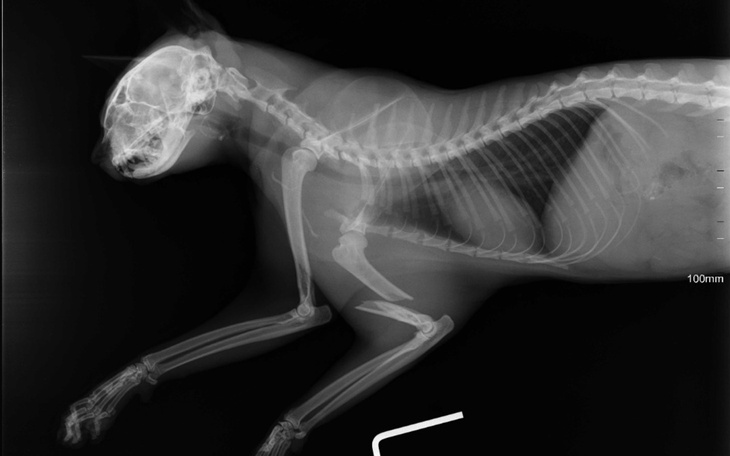

Po wstępnej diagnostyce wiemy już jedno – ma złamaną przednią łapkę. Każdy ruch to dla niego cierpienie. Każda próba postawienia kroku to ból, którego nie da się opisać.